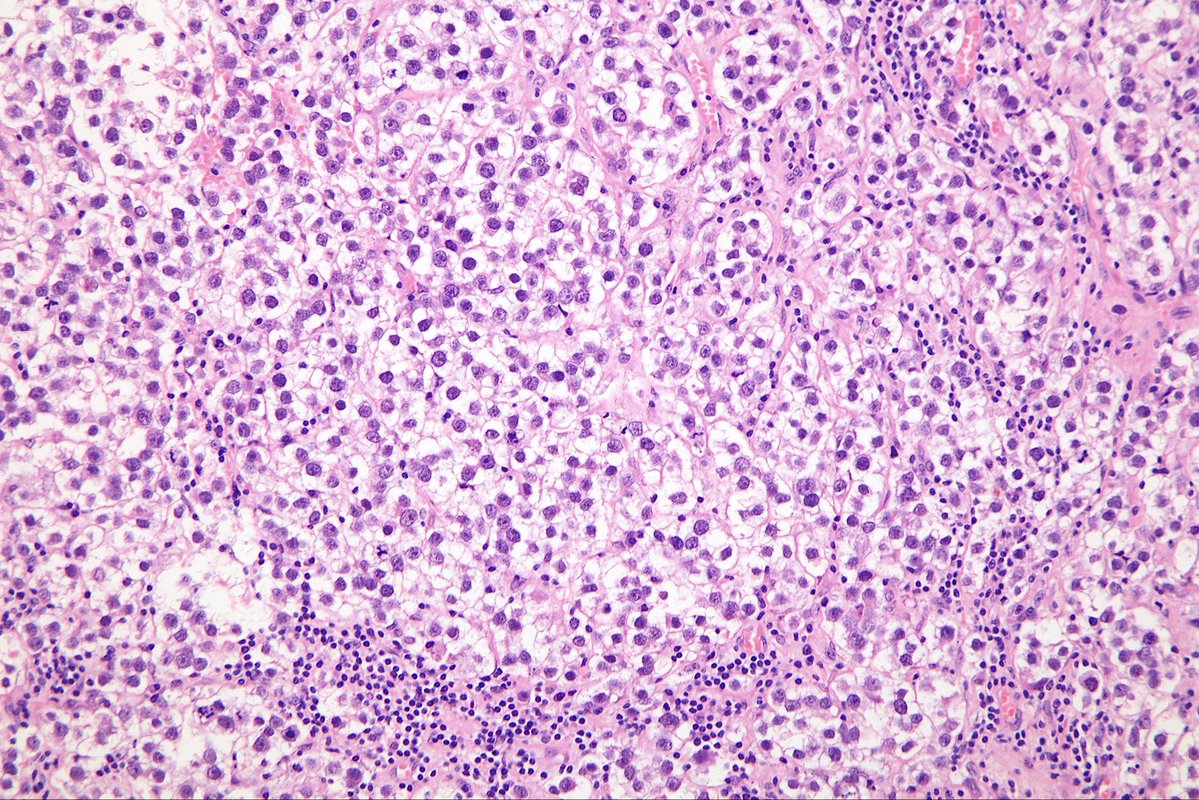

@MirunaPopescu13

DLBCL, NOS showing signet ring cell-like morphology. #hemepath #PathTwitter